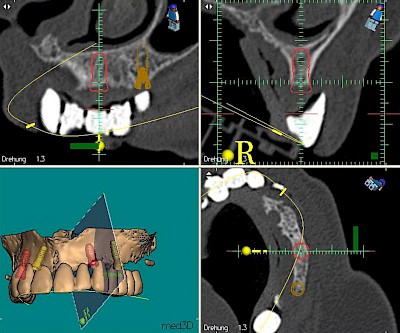

Implantatplanung

Damit Implantate an der richtigen Stelle im Kieferknochen platziert werden könen, gibt es heute vielfältige Möglichkeiten der Planung. In vielen Situationen kann die Erfahrung des Zahnarztes ausreichend sein.

Nicht selten ist jedoch auch eine technisch aufwändigere Vermessung im Vorfeld sinnvoll, z.B.:

- Wenn sich der Kieferknochen abgebaut hat

- Wenn der Nervverlauf im Unterkiefer beachtet werden muss

- Wenn die Ausdehung der Kieferhöhle im Oberkiefer beachtet werden muss

- Wenn wenige Restzähne keine gute Orientierung erlauben

In diesen Fällen kann die Planung mittels verschieden aufwendiger Röntgen-Techniken (Übersichtsaufnahme, DVT) ggf. unter Zuhilfenahme speziell angefertigter Planungsschablonen sinnvoll sein.

Beispiele15 Bilder

Knochenaufbau und Implantateinsatz

Ist nicht genügend Knochen zur Verankerung eines Implantates vorhanden, kann über einen sogenannten Knochenaufbau die Möglichkeit für das Einbringen eines Implantates geschaffen werden. Dazu kann z.B. Knochen aus der Kieferwinkelregion oder auch aus der Kinnregion entnommen und im Bereich der Fehlstellen aufgetragen werden. Auch künstliches Knochenmaterial kann dabei zum Einsatz kommen.

Im Oberkiefer wird – wenn ein Knochenaufbau notwendig ist – der Knochen in der Regel nicht außen "aufgelegt", sondern es wird der Boden der Kieferhöhle entweder über den Implantat-Bohrkanal durch Verdichtung nach oben gedrückt (interner Sinuslift) oder über eine Fensterung der vorderen knöchernen Kieferhöhlenwand kann Knochen im Bereich des Kieferhöhlenbodens eingebracht (externer Sinuslift).